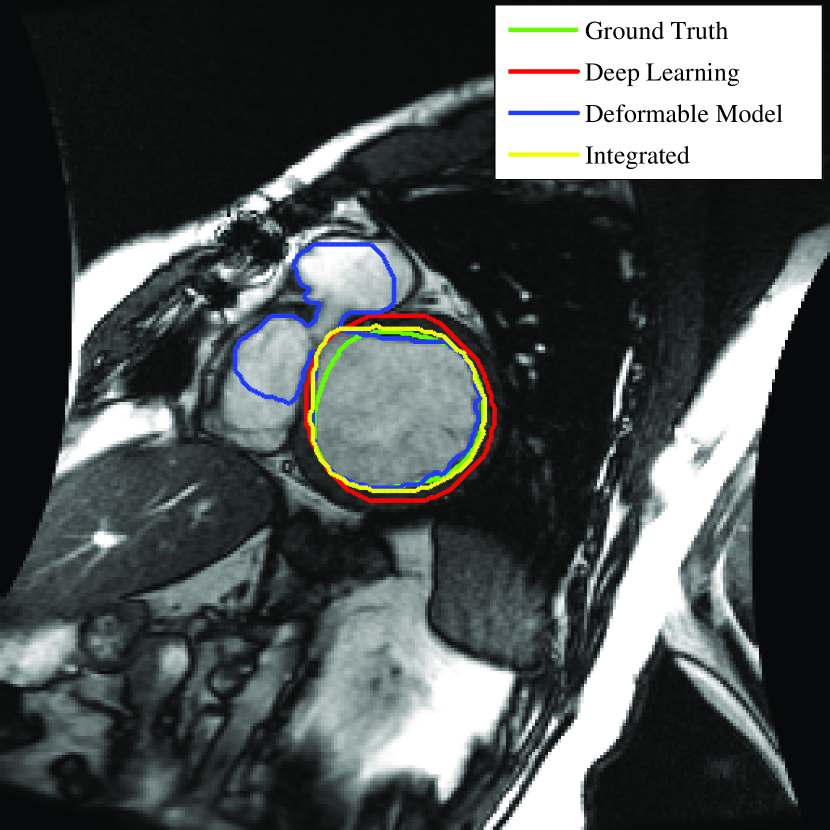

To better understand the role of each step, the outcome of the deformable model with no shape constraint (), deep learning (shape inference, Step 2) and the integrated deformable model and deep learning method (final step) for two typical images are shown in Fig. 8.

As seen in the left side of Fig. 8, the outcome of the deformable model without shape constraint (blue) leaked to surrounding tissues due to low contrast at the borders. Clearly this is not acceptable. On the other hand, the deep learning network (shape inference) provided a close contour (red) to the ground truth (green) with no leakage. This is due to the fact that the network has been trained using the ground truth data to look for the overall shape of the LV and not the intensity difference at the border. Finally, the integrated deep learning and deformable models brought the contour (yellow) closer to the ground truth. Similar behavior can be seen in the right side of Fig. 8 when contours tend to shrink due to presence of papillary muscles in the LV.